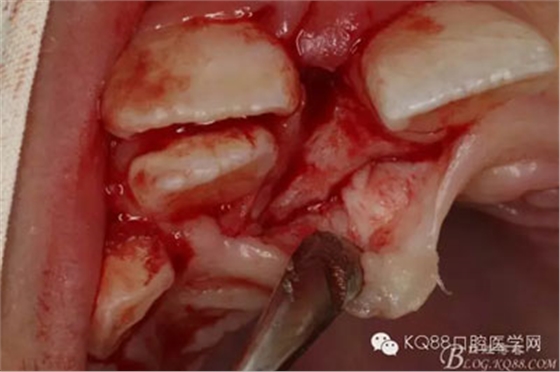

圖9.小骨鑿去骨后可見暴露的多生牙牙根,注意保護(hù)相鄰恒牙。

圖10.唇側(cè)使用微創(chuàng)挺挺松多生牙